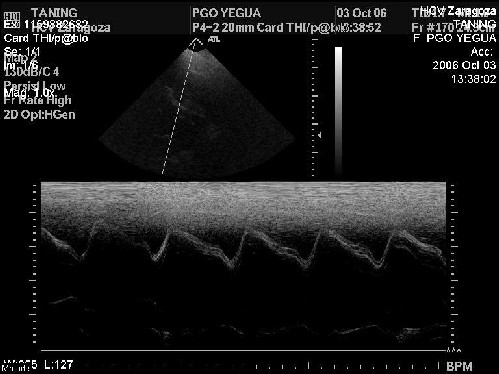

Ecocardiografía

La imagen 2, modo M se observa una buena dilatación del ventrículo izquierdo. Corte en eje corto parasternal derecho a nivel de músculos papilares. Esta imagen está normal y sirve para demostrar que el corazón se contrae y funciona bien.